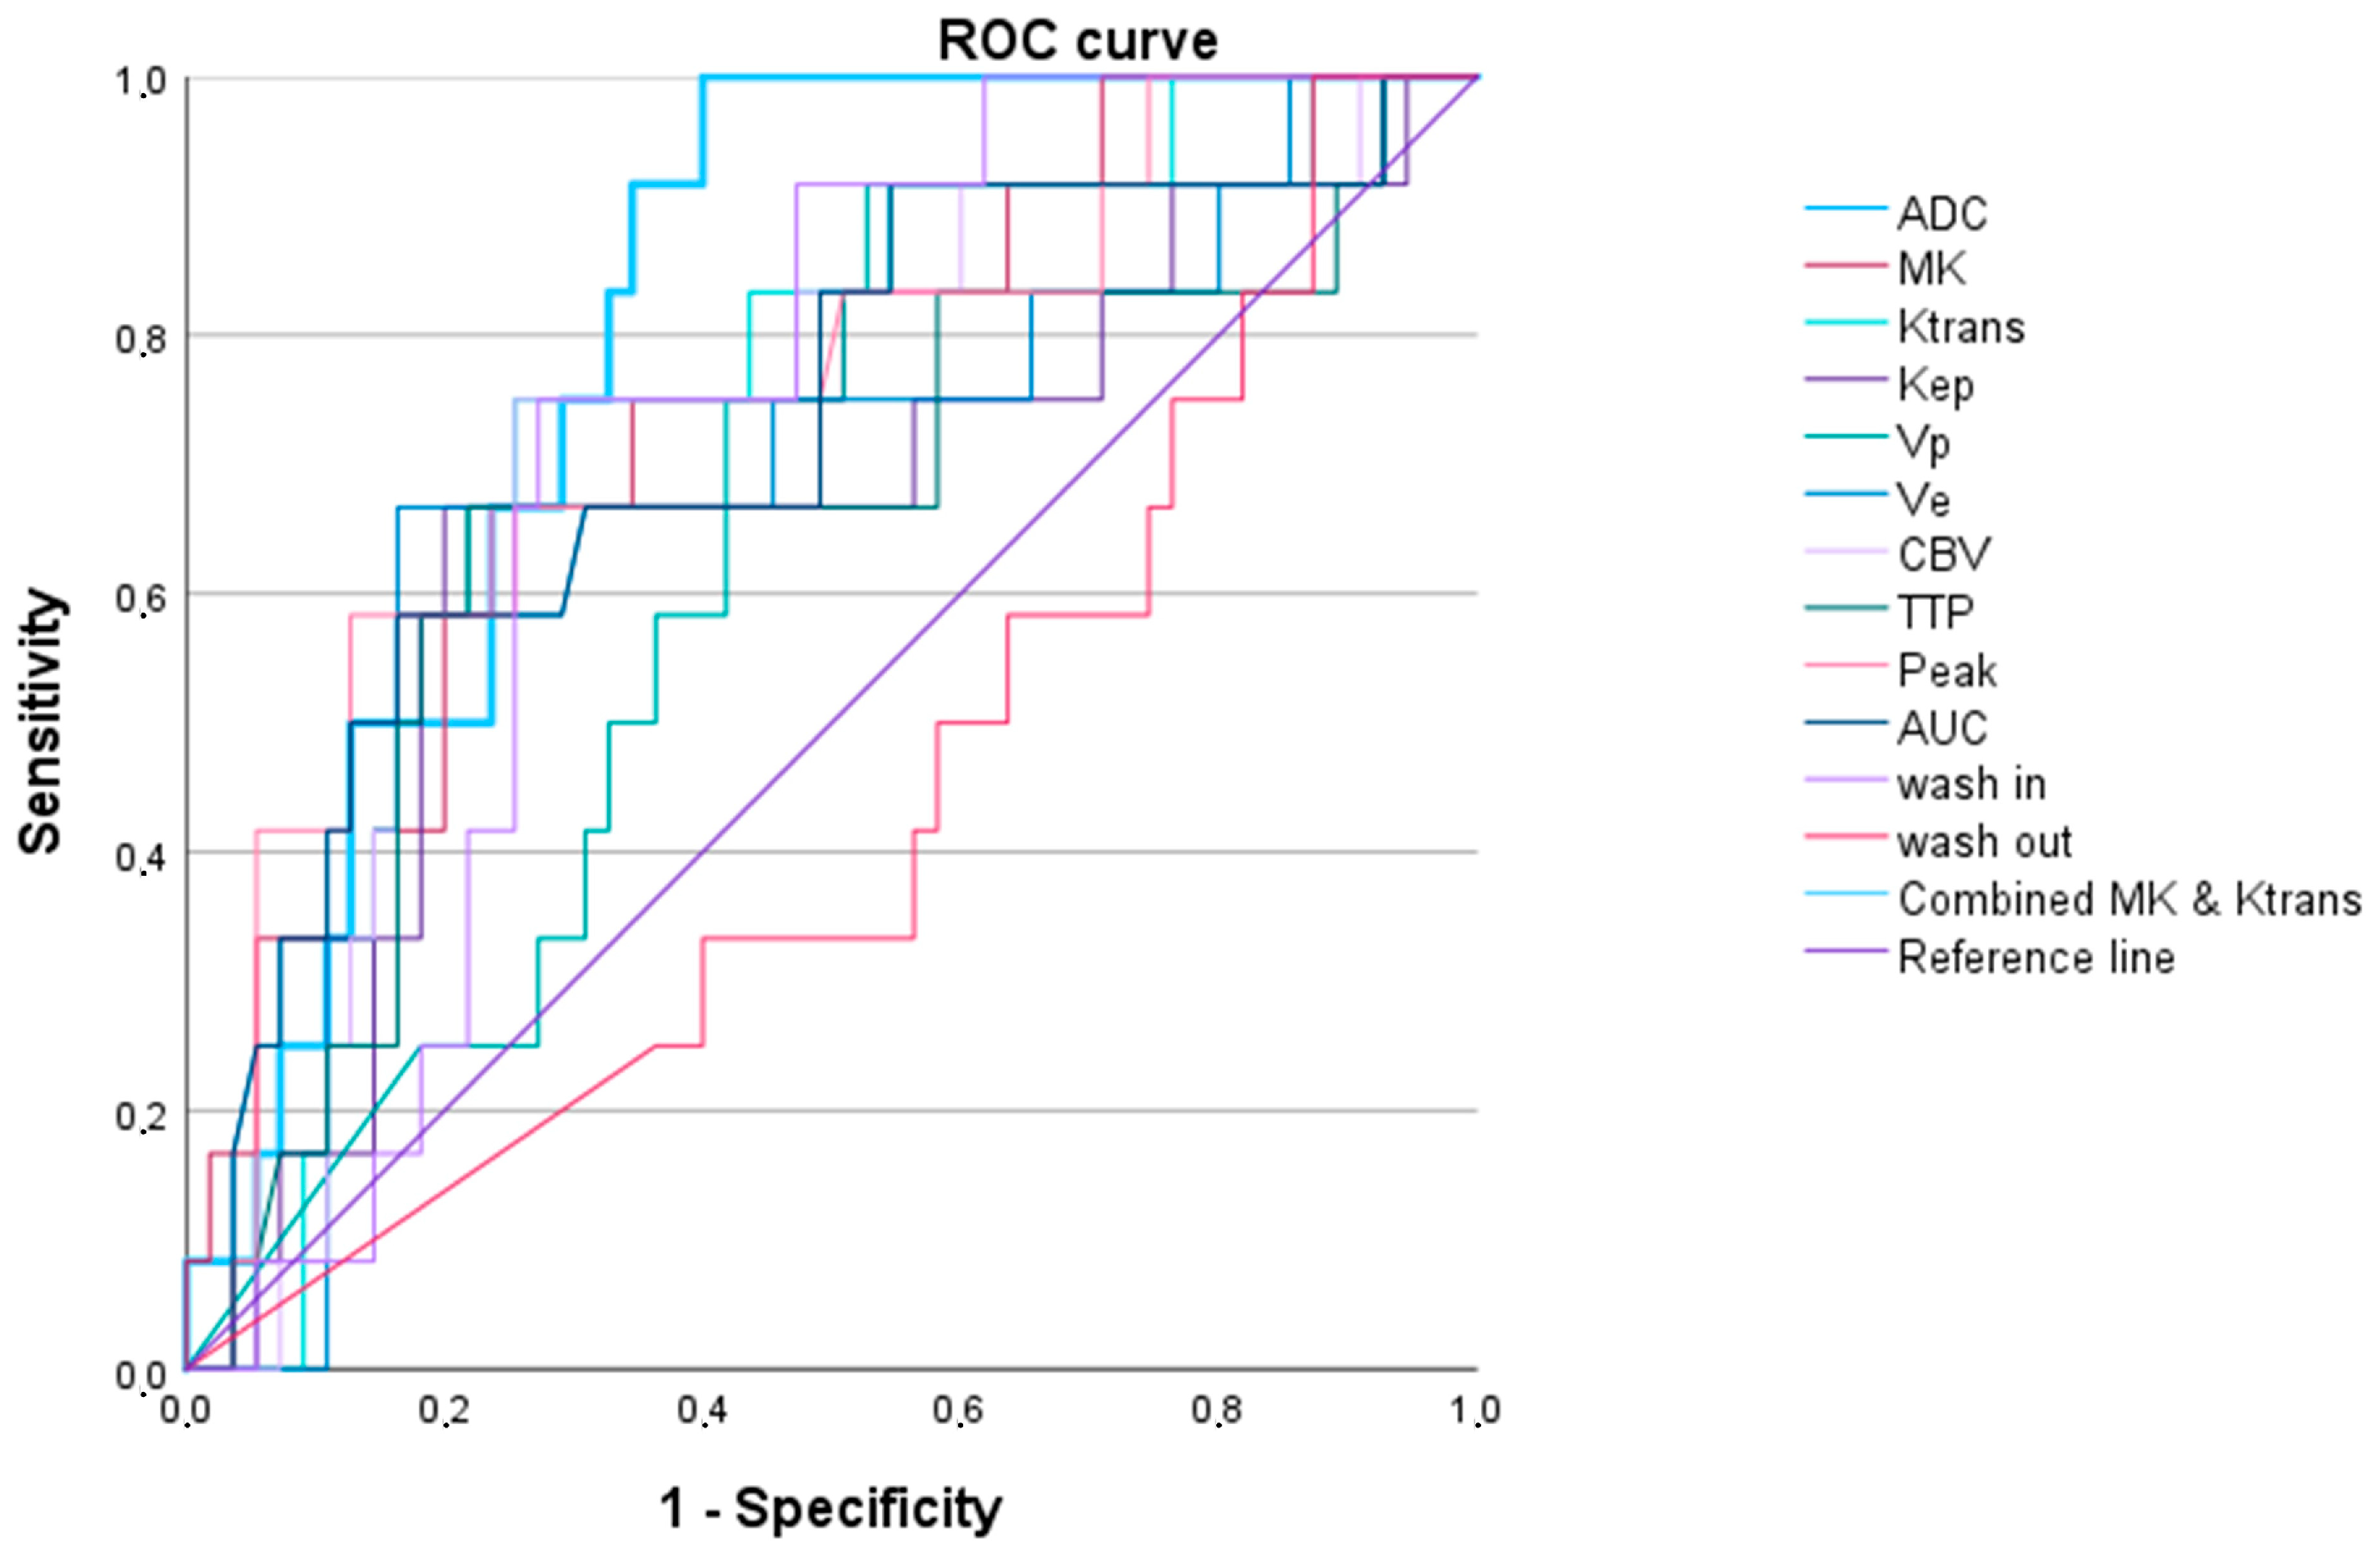

3.2. Evaluation of the Individual and Combined DCE-MRI and DKI Parameters

3.2.1. LGG versus HGG

3.2.2. IDH 1/2 Mutated versus IDH 1/2 Wildtype Gliomas

3.2.3. High-Grade Oligodendroglial versus High-Grade Astrocytic Gliomas

| WHO Grade 2 vs. WHO Grades 3 and 4 Adult-Type Gliomas | ||||||

|---|---|---|---|---|---|---|

| AUC (95% Confidence Interval) | p-Value | Cut-Off Value 1 | Sensitivity | Specificity | AIC | |

| Ktrans | 0.819 (0.695–0.944) | 0.001 | 1083.0 | 0.704 | 0.917 | 50.101 |

| Kep | 0.738 (0.538–0.938) | 0.010 | 388.4 | 0.704 | 0.833 | 53.158 |

| Vp | 0.610 (0.445–0.775) | 0.235 | 1272.1 | 0.444 | 0.917 | 62.937 |

| Ve | 0.885 (0.803–0.967) | <0.001 | 133.4 | 0.852 | 0.833 | 40.898 |

| CBV | 0.821 (0.682–0.960) | 0.001 | 827.9 | 0.778 | 0.833 | 50.917 |

| TTP | 0.902 (0.822–0.982) | <0.001 | 1769.4 | 0.685 | 1.000 | 43.158 |

| Peak | 0.895 (0.804–0.986) | <0.001 | 11.9 | 0.889 | 0.883 | 41.096 |

| AUCDCE | 0.910 (0.840–0.980) | <0.001 | 76.2 | 0.759 | 1.000 | 37.911 |

| wash in | 0.860 (0.761–0.958) | <0.001 | 13,334.5 | 0.759 | 0.917 | 45.400 |

| wash out | 0.631 (0.461–0.801) | 0.158 | 4.3 | 0.463 | 0.833 | 60.495 |

| ADC | 0.844 (0.732–0.956) | <0.001 | 542.1 | 0.741 | 0.833 | 48.012 |

| MK | 0.884 (0.788–0.981) | <0.001 | 551.5 | 0.852 | 0.750 | 41.893 |

| TTP and ADC 2 | 0.954 (0.900–1.000) | <0.001 | 0.8 | 0.889 | 0.917 | 28.532 |

| IDH1/2 Wildtype vs. IDH1/2 Mutated Adult-Type Gliomas | ||||||

|---|---|---|---|---|---|---|

| AUC (95% Confidence Interval) | p-Value | Cut-Off Value 1 | Sensitivity | Specificity | AIC | |

| Ktrans | 0.731 (0.614–0.849) | 0.001 | 1692.2 | 0.810 | 0.594 | 89.848 |

| Kep | 0.710 (0.588–0.831) | 0.002 | 842.3 | 0.667 | 0.750 | 91.636 |

| Vp | 0.583 (0.441–0.724) | 0.226 | 1303.0 | 0.833 | 0.500 | 99.564 |

| Ve | 0.726 (0.604–0.848) | 0.001 | 366.3 | 0.643 | 0,781 | 94.220 |

| CBV | 0.738 (0.622–0.854) | <0.001 | 1734.6 | 0.810 | 0.625 | 91.196 |

| TTP | 0.685 (0.562–0.807) | 0.007 | 2000.3 | 0.714 | 0.688 | 95.088 |

| Peak | 0.738 (0.625–0.850) | <0.001 | 13.0 | 0.500 | 0.938 | 94.056 |

| AUCDCE | 0.791 (0.609–0.891) | <0.001 | 118.8 | 0.762 | 0.688 | 83.677 |

| wash in | 0.718 (0.602–0.834) | 0.001 | 439.5 | 0.619 | 0.813 | 92.798 |

| wash out | 0.555 (0.419–0.692) | 0.416 | 1.0 | 0.786 | 0.406 | 103.058 |

| ADC | 0.699 (0.576–0.821) | 0.004 | 468.8 | 0.738 | 0.656 | 94.858 |

| MK | 0.718 (0.601–0.835) | 0.001 | 620.9 | 0.595 | 0.781 | 91.430 |

| AUCDCE and MK 2 | 0.802 (0.702–0.903) | <0.001 | 0.6 | 0.762 | 0.759 | 80.982 |

| Oligodendroglioma (IDH1/2 Mutated 1p/19q Codeletion) (WHO Grade 3) vs. Glioblastoma IDH1/2 Wildtype (WHO Grade 4) and Astrocytoma IDH1/2 Mutated (WHO Grades 3 and 4) | ||||||

|---|---|---|---|---|---|---|

| AUC (95% Confidence Interval) | p Value | Cut-Off Value 1 | Sensitivity | Specificity | AIC | |

| Ktrans | 0.739 (0.598–0.880) | 0.010 | 834.1 | 0.750 | 0.745 | 57.060 |

| Kep | 0.655 (0.471–0.838) | 0.095 | 1665.0 | 0.667 | 0.800 | 60.861 |

| Vp | 0.642 (0.490–0.795) | 0.124 | 1269.2 | 0.917 | 0.436 | 61.163 |

| Ve | 0.680 (0.505–0.855) | 0.052 | 134.7 | 0.667 | 0.836 | 62.006 |

| CBV | 0.720 (0.561–0.878) | 0.018 | 900.6 | 0.750 | 0.745 | 59.183 |

| TTP | 0.660 (0.473–0.847) | 0.085 | 669.4 | 0.667 | 0.782 | 60.728 |

| Peak | 0.733 (0.571–0.894) | 0.012 | 10.9 | 0.583 | 0.873 | 58.150 |

| AUCDCE | 0.721 (0.555–0.887) | 0.017 | 41.4 | 0.583 | 0.836 | 61.297 |

| wash in | 0.715 (0.587–0.843) | 0.020 | 471.6 | 0.750 | 0.727 | 57.818 |

| wash out | 0.433 (0.262–0.605) | 0.472 | 44.0 | 1.000 | 0.127 | 64.886 |

| ADC | 0.721 (0.555–0.887) | 0.054 | 505.4 | 0.583 | 0.836 | 60.645 |

| MK | 0.741 (0.592–0.890) | 0.009 | 658.3 | 0.750 | 0.655 | 57.369 |

| Ktrans and MK 2 | 0.806 (0.700–0.912) | <0.001 | 0.1 | 1.000 | 0.600 | 54.839 |